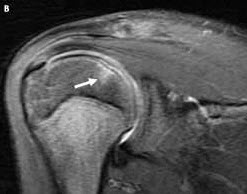

MRI of the right shoulder showed a subchondral crescent-shaped area of signal abnormality on the superomedial portion of the humeral head (A, black arrow) along with subchondral edema (B, white arrow). The appearance of the signal abnormality, along with the underlying edema, is consistent with an osteochondral fracture of the humeral head.